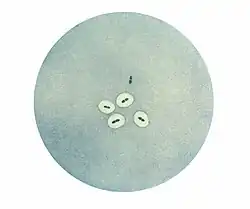

The quellung reaction, also called the Neufeld reaction, is a biochemical reaction in which antibodies bind to the bacterial capsule of Streptococcus pneumoniae, Klebsiella pneumoniae, Neisseria meningitidis, Bacillus anthracis, Haemophilus influenzae,[1] Escherichia coli, and Salmonella. The antibody reaction allows these species to be visualized under a microscope. If the reaction is positive, the capsule becomes opaque and appears to enlarge.

Quellung is the German word for "swelling" and describes the microscopic appearance of pneumococcal or other bacterial capsules after their polysaccharide antigen has combined with a specific antibody. The antibody usually comes from serum taken from an immunized laboratory animal. As a result of this combination, and precipitation of the large, complex molecule formed, the capsule appears to swell, because of increased surface tension, and its outlines become demarcated.